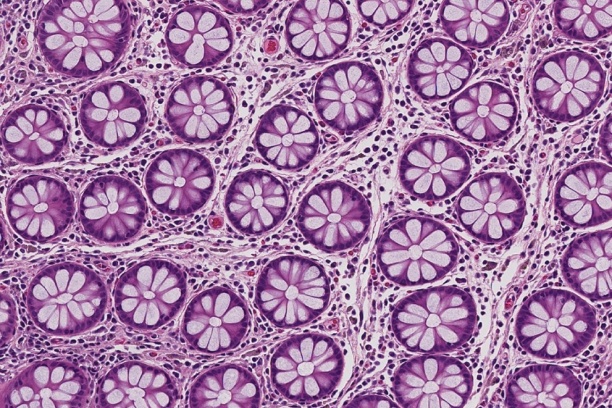

The Digital Histology Shared Resource provides large-scale digital archiving and quantitative analysis of histologic, immunohistochemical and immunofluorescence staining of tissue sections and tissue microarrays. Two Aperio Versa automated scanning microscopes, and Aperio AT2 and a Leica SCN400 Slide Scanner deliver solutions for high-resolution imaging in both bright field and fluorescence. All instruments have high-capacity robotic autoloading (200 slides for the Aperio Versa and Aperio AT2 and 384 slides for the Leica SCN400) making them ideal for large slide cohorts and tissue microarrays. The associated software packages provide complex algorithms for unbiased, automated image analysis and quantitation of immunostaining in both bright field and fluorescence. In addition, these systems can be utilized as a permanent high-resolution solution for those who need archiving of histologic material. The DHSR hosts a convenient, web-based digital slide-viewing environment (Digital Slide Archive) for the rapid retrieval, review, annotation and image acquisition of scanned material. This easy to use digital slide box allows researchers to share images among colleagues from any web browser while remaining in a digitally secure environment. Expert assistance is offered in planning experiments and processing data in a consistent, objective, and timely manner. The automated imaging and analysis performed in this core saves researchers and staff weeks of tedious work. An additional service offered by the DHSR is the creation of digital archives of critical and irreplaceable tissue samples, a benefit only feasible due to the automated high-resolution imaging of whole 25 mm x 75 mm microscope slides and 50 mm x 75 mm "double" slides.

The DHSR offers specialized microscopy assistance in addition to automated slide scanning and analysis, such as colony counting. The core is capable of high-resolution automated and semi-automated imaging and quantitation of a wide range of cell culture and tissue samples, from bacterial colonies to organoids. The GelCount• system by Oxford Optronix scans and counts mammalian cells, yeast or bacterial colonies in a wide variety of Petri dish and cell culture plate formats. This system is designed for the detection, counting and characterization of stained/adherent mammalian cell colonies or of unstained/non-adherent colonies in soft agar or collagen assays, but also works very well for yeast and bacterial colonies. The software is fully trainable and can be programmed to recognize specific colony features. Detailed information such as diameter, area, density, and nearest neighbor is provided, as well as high-resolution images.